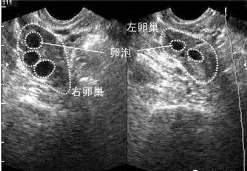

To:卵巢健康对试管婴儿成功率有影响吗?学好5招

如今,随着试管婴儿技术的发展,大多数不孕不育夫妇都会选择做试管婴儿来帮助自己怀孕,而且随着试管婴儿